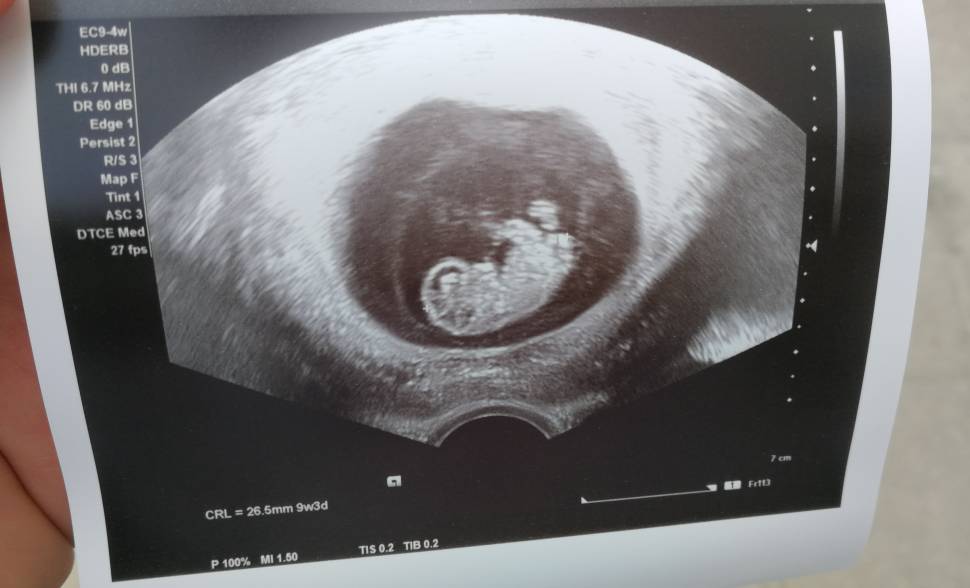

Nasze USG

Mój człowieczek malutki [emoji3590] niecałe 3cm, tętno 171. No kocham go/ją już [emoji28]

IMG_20190301_133242.jpeg